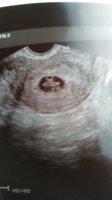

Kävin ultrassa, löytyi sikiö ja sykekin mahdollisesti (oma sykekin korkea niin saattoi sekoittua). Kontrolliultra on 12.8. ja hcg-mittaukset myös tänään ja silloin ennen seuraavaa ultraa. Sikiö oli 3,4 mm eli tosi varhaista on vielä, se noin 6 viikkoa korkeintaan.

Ultrassa käyty ja syke löytyi ihan oikeasta paikasta kooltaan vastasi 6+6 vaikka piti olla 7+2 mutta yritän olla tuosta nyt huolehtimatta!

Meilläkin varhaisultrassa piti olla viikkoja 7+6, mutta löytyikin 6+4 vastaava tyyppi. Kätilö ja neuvola ovat sitä mieltä, että ei saisi huolestua. Kerta syke löytynyt oikeasta paikasta, mutta kyllä se itseä vaivaa. Vaikka toki ainakin itellä toi selittää sen, miksi raskaustesti näytti vasta viikkoa myöhemmin plussaa, kun olisi pitänyt.